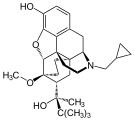

Oripavine derivatives

Thienorphine

- 7-PET

- Acetorphine

- Alletorphine (N-allyl-noretorphine)

- BU-48

- Buprenorphine

- Buprenorphine-3-glucuronide

- Cyprenorphine

- Dihydroetorphine

- Etorphine

- Homprenorphine

- 18,19-Dehydrobuprenorphine (HS-599)

- N-cyclopropylmethylnoretorphine

- Nepenthone

- Norbuprenorphine

- Norbuprenorphine-3-glucuronide

- Thevinone

- Thienorphine

Structures

| Oripavine derivatives | ||||

7-PET 7-PET |

Acetorphine Acetorphine |

Alletorphine Alletorphine |

BU-48 BU-48 |

Buprenorphine Buprenorphine |

Cyprenorphine Cyprenorphine |

Dihydroetorphine Dihydroetorphine |

Etorphine Etorphine |

Homprenorphine Homprenorphine |

18,19-Dehydrobuprenorphine 18,19-Dehydrobuprenorphine |

N-cyclopropylmethylnoretorphine N-cyclopropylmethylnoretorphine |

Nepenthone Nepenthone |

Norbuprenorphine Norbuprenorphine |

Thevinone Thevinone |

Thienorphine Thienorphine |